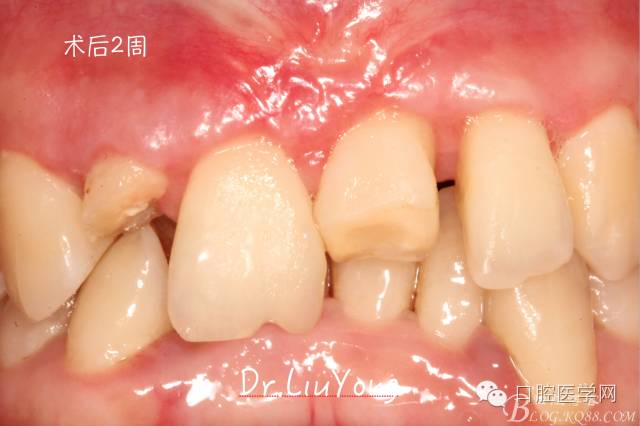

術(shù)后兩周,復(fù)查,A1達到了完全的根面覆蓋,B1牙齦退縮由原來的3.5mm減少到1mm,B2近中牙齦也得到部分的恢復(fù),同時所有牙齦邊緣都通過手術(shù)增厚。如上圖